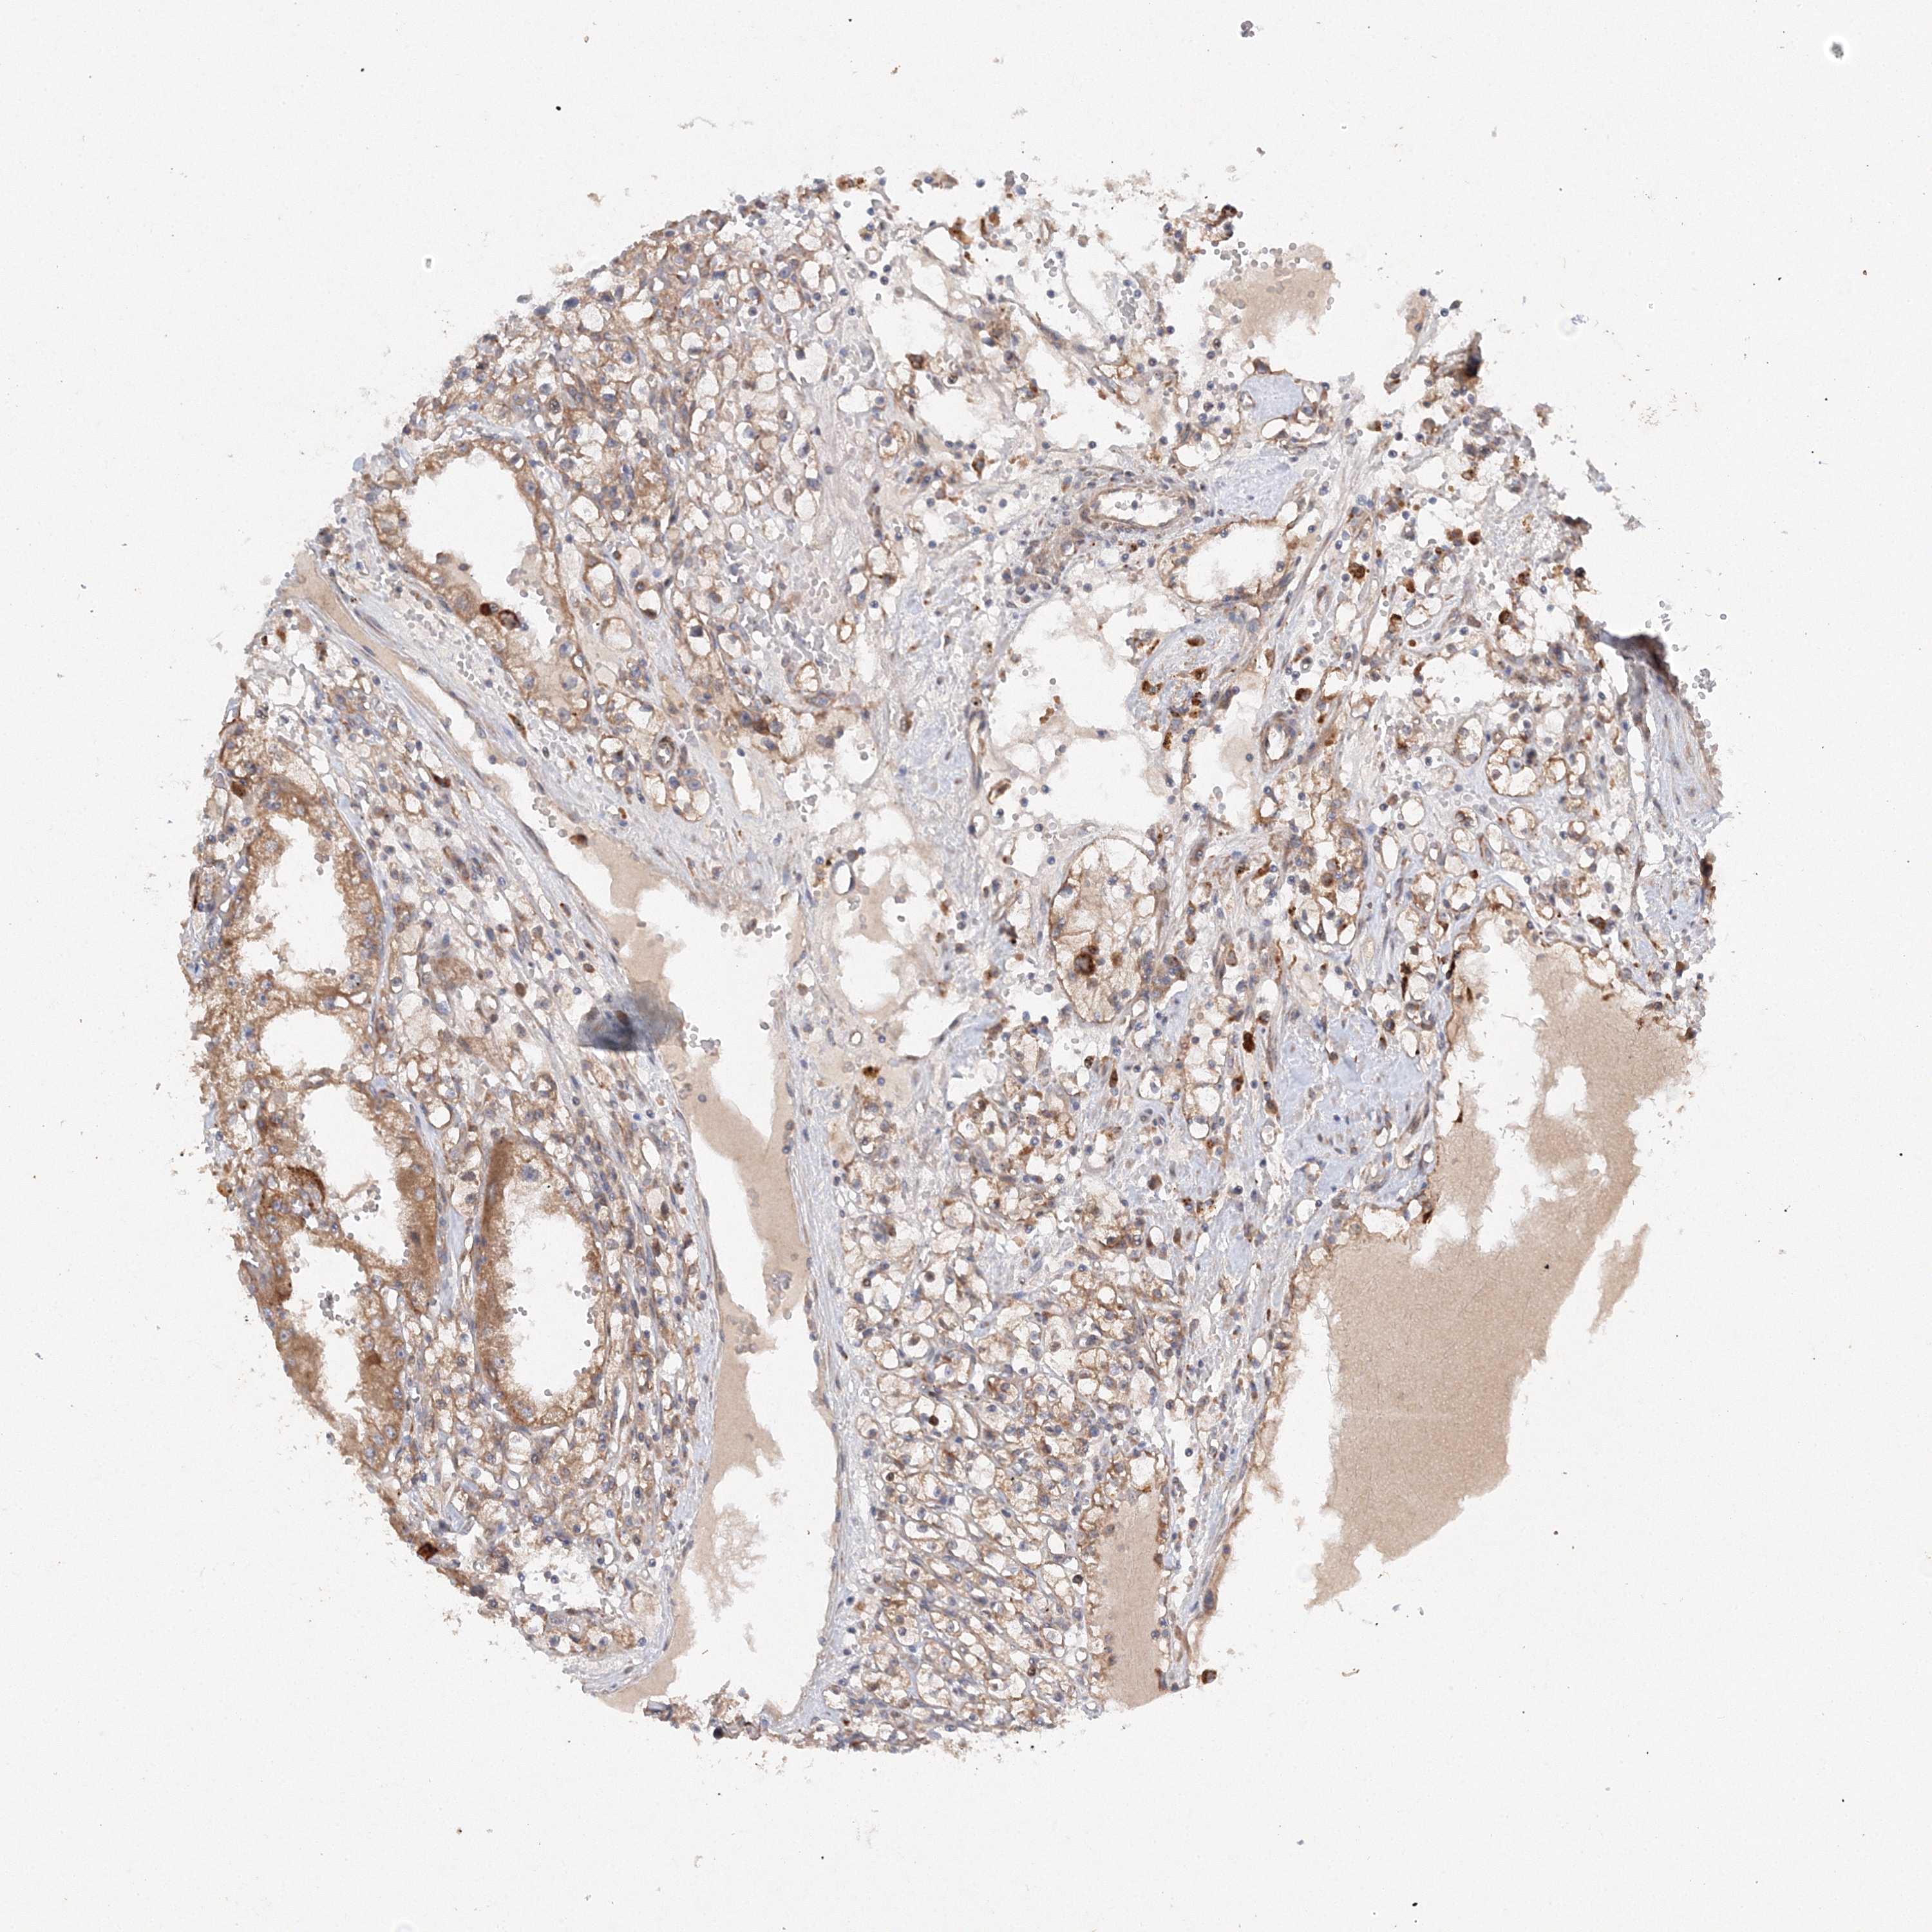

KIDNEY RENAL PAPILLARY CELL CARCINOMA (TCGA) - Interactive survival scatter ploti

The Survival Scatter plot shows the clinical status (i.e. dead or alive) for all individuals in the patient cohort, based on the same data that underlies the corresponding Kaplan-Meier plots. Patients that are alive at last time for follow-up are shown in blue and patients who have died during the study are shown in red.

The x-axis shows the expression levels (FPKM) of the investigated gene in the tumor tissue at the time of diagnosis. The y-axis shows the follow-up time after diagnosis (years). Both axes are complimented with kernel density curves demonstrating the data density over the axes. The top density plot shows the expression levels (FPKM) distribution among dead (red) and alive patients (blue). The right density plot shows the data density of the survived years of dead patients with high and low expression levels respectively, stratified using the cutoff indicated by the vertical dashed line through the Survival Scatter plot. This cutoff is automatically defined based on the FPKM cutoff that minimizes the p-score. The cutoff can be changed by dragging the vertical line or by entering a cutoff value in the square labeled "Current cut-off".

Under the Survival Scatter plot the p-score landscape (black curve; left axis) is shown together with dead median separation (red curve; right axis). Dead median separation is the difference in median mRNA expression between patients who have died with high and low expression, respectively. It is calculated as follows: median FPKM expression of dead patients with high expression - median FPKM expression of dead patients with low expression. This is intended to aid the user in visually exploring custom cutoffs and the associated p-scores and dead median separation.

Individual patient data is displayed and can be filtered by clicking on one or more of the category buttons on the top of the page. Categories describing expression level and patient information include: high, low, alive, dead, female, male and tumor stages. The scale of the x-axis can be toggled between linear and log-scale by clicking on the "x log" button. Mouse-over function shows TCGA ID, patient information and mRNA expression (FPKM) for each patient.

& Survival analysisi

Kaplan-Meier plots summarize results from analysis of correlation between mRNA expression level and patient survival. Patients were divided based on level of expression into one of the two groups "low" (under cut off) or "high" (over cut off). X-axis shows time for survival (years) and y-axis shows the probability of survival, where 1.0 corresponds to 100 percent.

SLC36A1 is not prognostic in Kidney Renal Papillary Cell Carcinoma (TCGA)

Best expression cut offi

Based on the FPKM value of each gene, patients were classified into two groups and association between prognosis (survival) and gene expression (FPKM) was examined. The best expression cut-off refers the FPKM value that yields maximal difference with regard to survival between the two groups at the lowest log-rank P-value. Best expression cut-off was selected based on survival analysis .